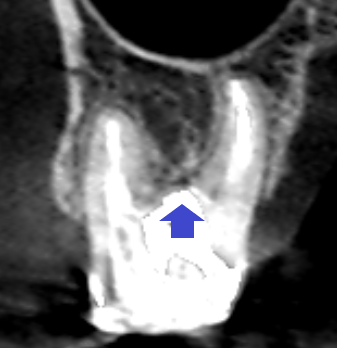

上顎第一大臼歯の初診時の矢状断のCT画像です。

赤い矢印の先の近心頬側根の先に膿の影がみられます。